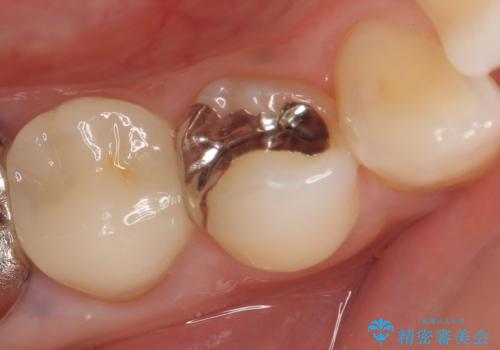

- 甘いものを食べると右下4番目の歯がしみるので診て欲しいといらっしゃった方の症例です。

古い銀歯と虫歯を除去後、PGA(ゴールド)インレーによる修復を行いました。